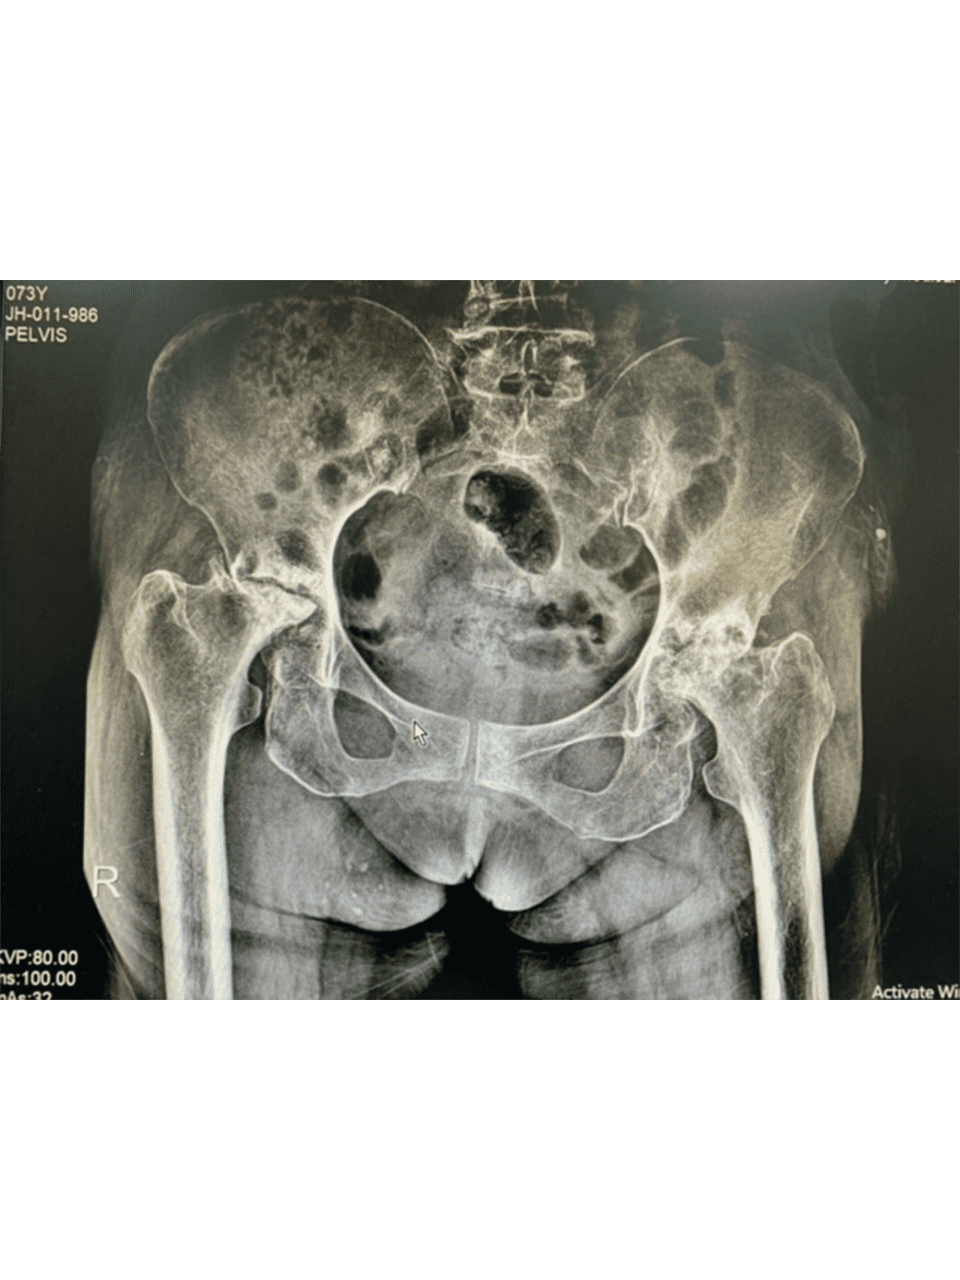

Dr. Weber and his partners participate in short term medical mission trips to Cambodia. Dr. Weber has had the pleasure of going twice now in 2018 and 2020. During these trips Dr. Weber performs total hip replacements on patients who normally would have no treatment options. To learn more and to see videos from the experience please click the links below.